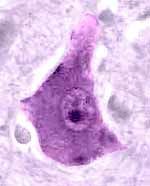

Dendrite Transmit graded potentials towards the cell body

Cell body/ soma Transmit graded potential to the axon

axon conducts electrical impulses away from neuron's cell body